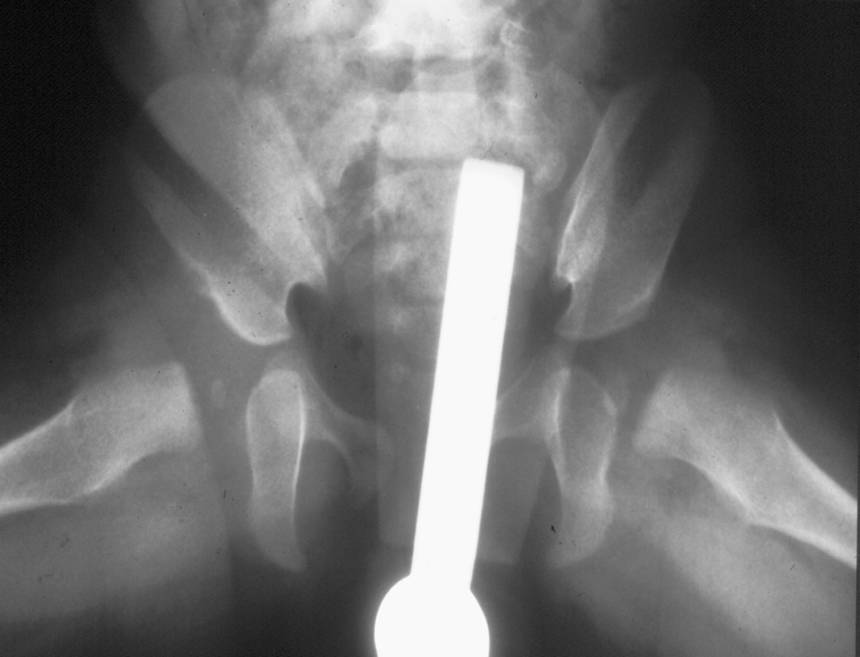

La radiografia è un esame di secondo livello nello studio della DCA. È limitata allo studio dell’osso senza evidenziare i tessuti molli, per questo è riservata nei pazienti dai 4-6 mesi d’età, o che sono già in trattamento.

La centrazione viene ottenuta attraverso il confezionamento di gessi pelvi-podalici modellati in anestesia generale, preceduti o meno da una trazione progressiva dell’arto inferiore.

Quest’ultima, riservata soprattutto ai casi di Lussazione dell’Anca (LCA), è eseguita in ambiente ospedaliero sotto uno stretto controllo medico-infermieristico.